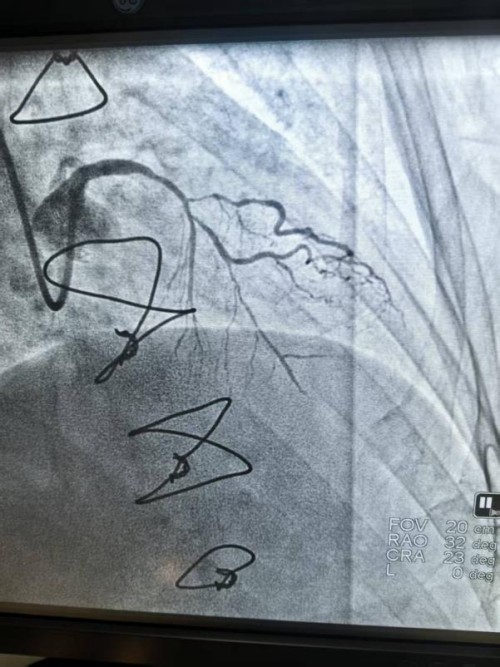

入院后,彭文华主任团队为刘大爷进行了全面检查。冠脉造影结果让医生们皱起了眉头:之前搭的桥血管是通畅的,但心脏自身的重要血管(前降支至对角支)出现了严重的狭窄,狭窄程度超过90%。更棘手的是,这个狭窄部位伴随着严重的钙化。通俗点说,就是血管壁里沉积了厚厚的“钙质”,像水管里结满了坚硬的水垢,甚至像在血管里筑起了“钢筋水泥”,让普通的介入器械难以通过,强行处理风险极高。

造影图像清晰地显示,病变处的钙化长且弥漫,呈管状钙化影。而且是深埋在血管壁中层的“深层钙化”。面对如此复杂的病情,常规的球囊扩张就像用普通气球去撑开一块石头,不仅可能撑不开,还容易把血管壁撑破,导致夹层、穿孔等严重并发症。

在4个大气压的低压下,球囊开始工作,释放出脉冲式冲击波。“砰、砰、砰……”伴随着几十次轻柔的脉冲,冲击波能量穿透血管,直抵深处的钙化病灶。术后再次用造影查看,效果立竿见影。血管管腔瞬间变得宽敞了许多,而且血管壁完好无损,没有出现任何夹层或损伤。